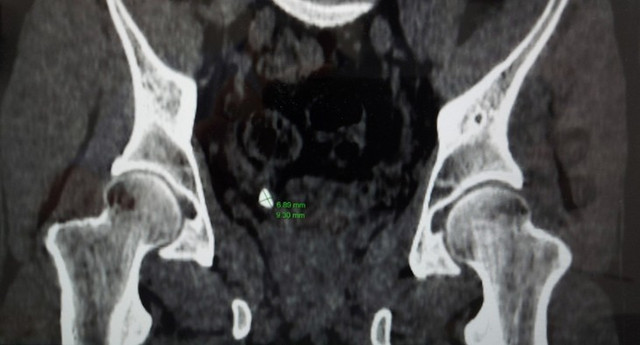

Ngay lập tức, người bệnh được các bác sĩ chỉ định làm các xét nghiệm, siêu âm bụng, chụp cắt lớp vi tính và xác định người bệnh bị sỏi niệu quản phải 1/3 dưới (nằm ở vị trí đoạn nối của niệu quản khi vào tới bàng quang), sỏi kích thước xấp xỉ 9x7mm.

Hình ảnh thận của bệnh nhân trên phim chụp - Ảnh: BVCC

Bất ngờ hơn, kết quả chụp CT các bác sĩ phát hiện người bệnh có thận niệu quản đôi hoàn toàn hai bên trái, phải và hai niệu quản riêng biệt đều cắm xuống bàng quang. Người bệnh có bất thường về giải phẫu hệ tiết niệu, có nhiều đơn vị thận hơn bình thường là một trong những nguyên nhân hình thành sỏi thận.

Sỏi thận trong cơ thể người bệnh trên phim chụp - Ảnh BVCC